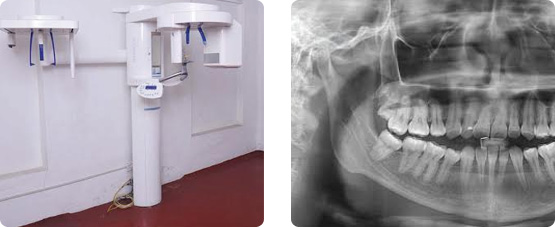

An OPG is a panoramic or wide view x-ray of the lower face, which displays all the teeth of the upper and lower jaw on a single film. It demonstrates the number, position and growth of all the teeth including those that have not yet surfaced or erupted.